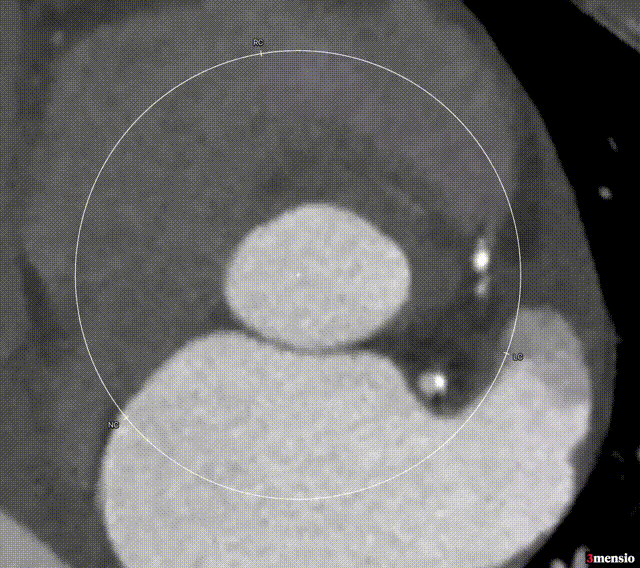

根部整体结构1

瓣环面积 607.5mm²,LVOT面积 652.6mm²

SOV直径:Distance L:41 mm;Distance R:34.8mm;Distance N:41mm

升主动脉严重增宽:Area derived:59.6mm

左冠高度14.3mm,右冠高度23.3mm,模拟25mm RENATUS瓣膜植入,评估冠脉风险较低。

钙化情况:850阈值:钙化积分1268mm³。

横位心,主动脉瓣环与水平面夹角67°。

血管入路评估:主动脉弓部角度小,右侧股动脉最细 7mm,左侧股动脉最细7.3mm。双侧股动脉穿刺点无明显钙化。